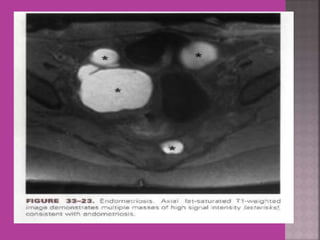

Ovarian Endometriomaa